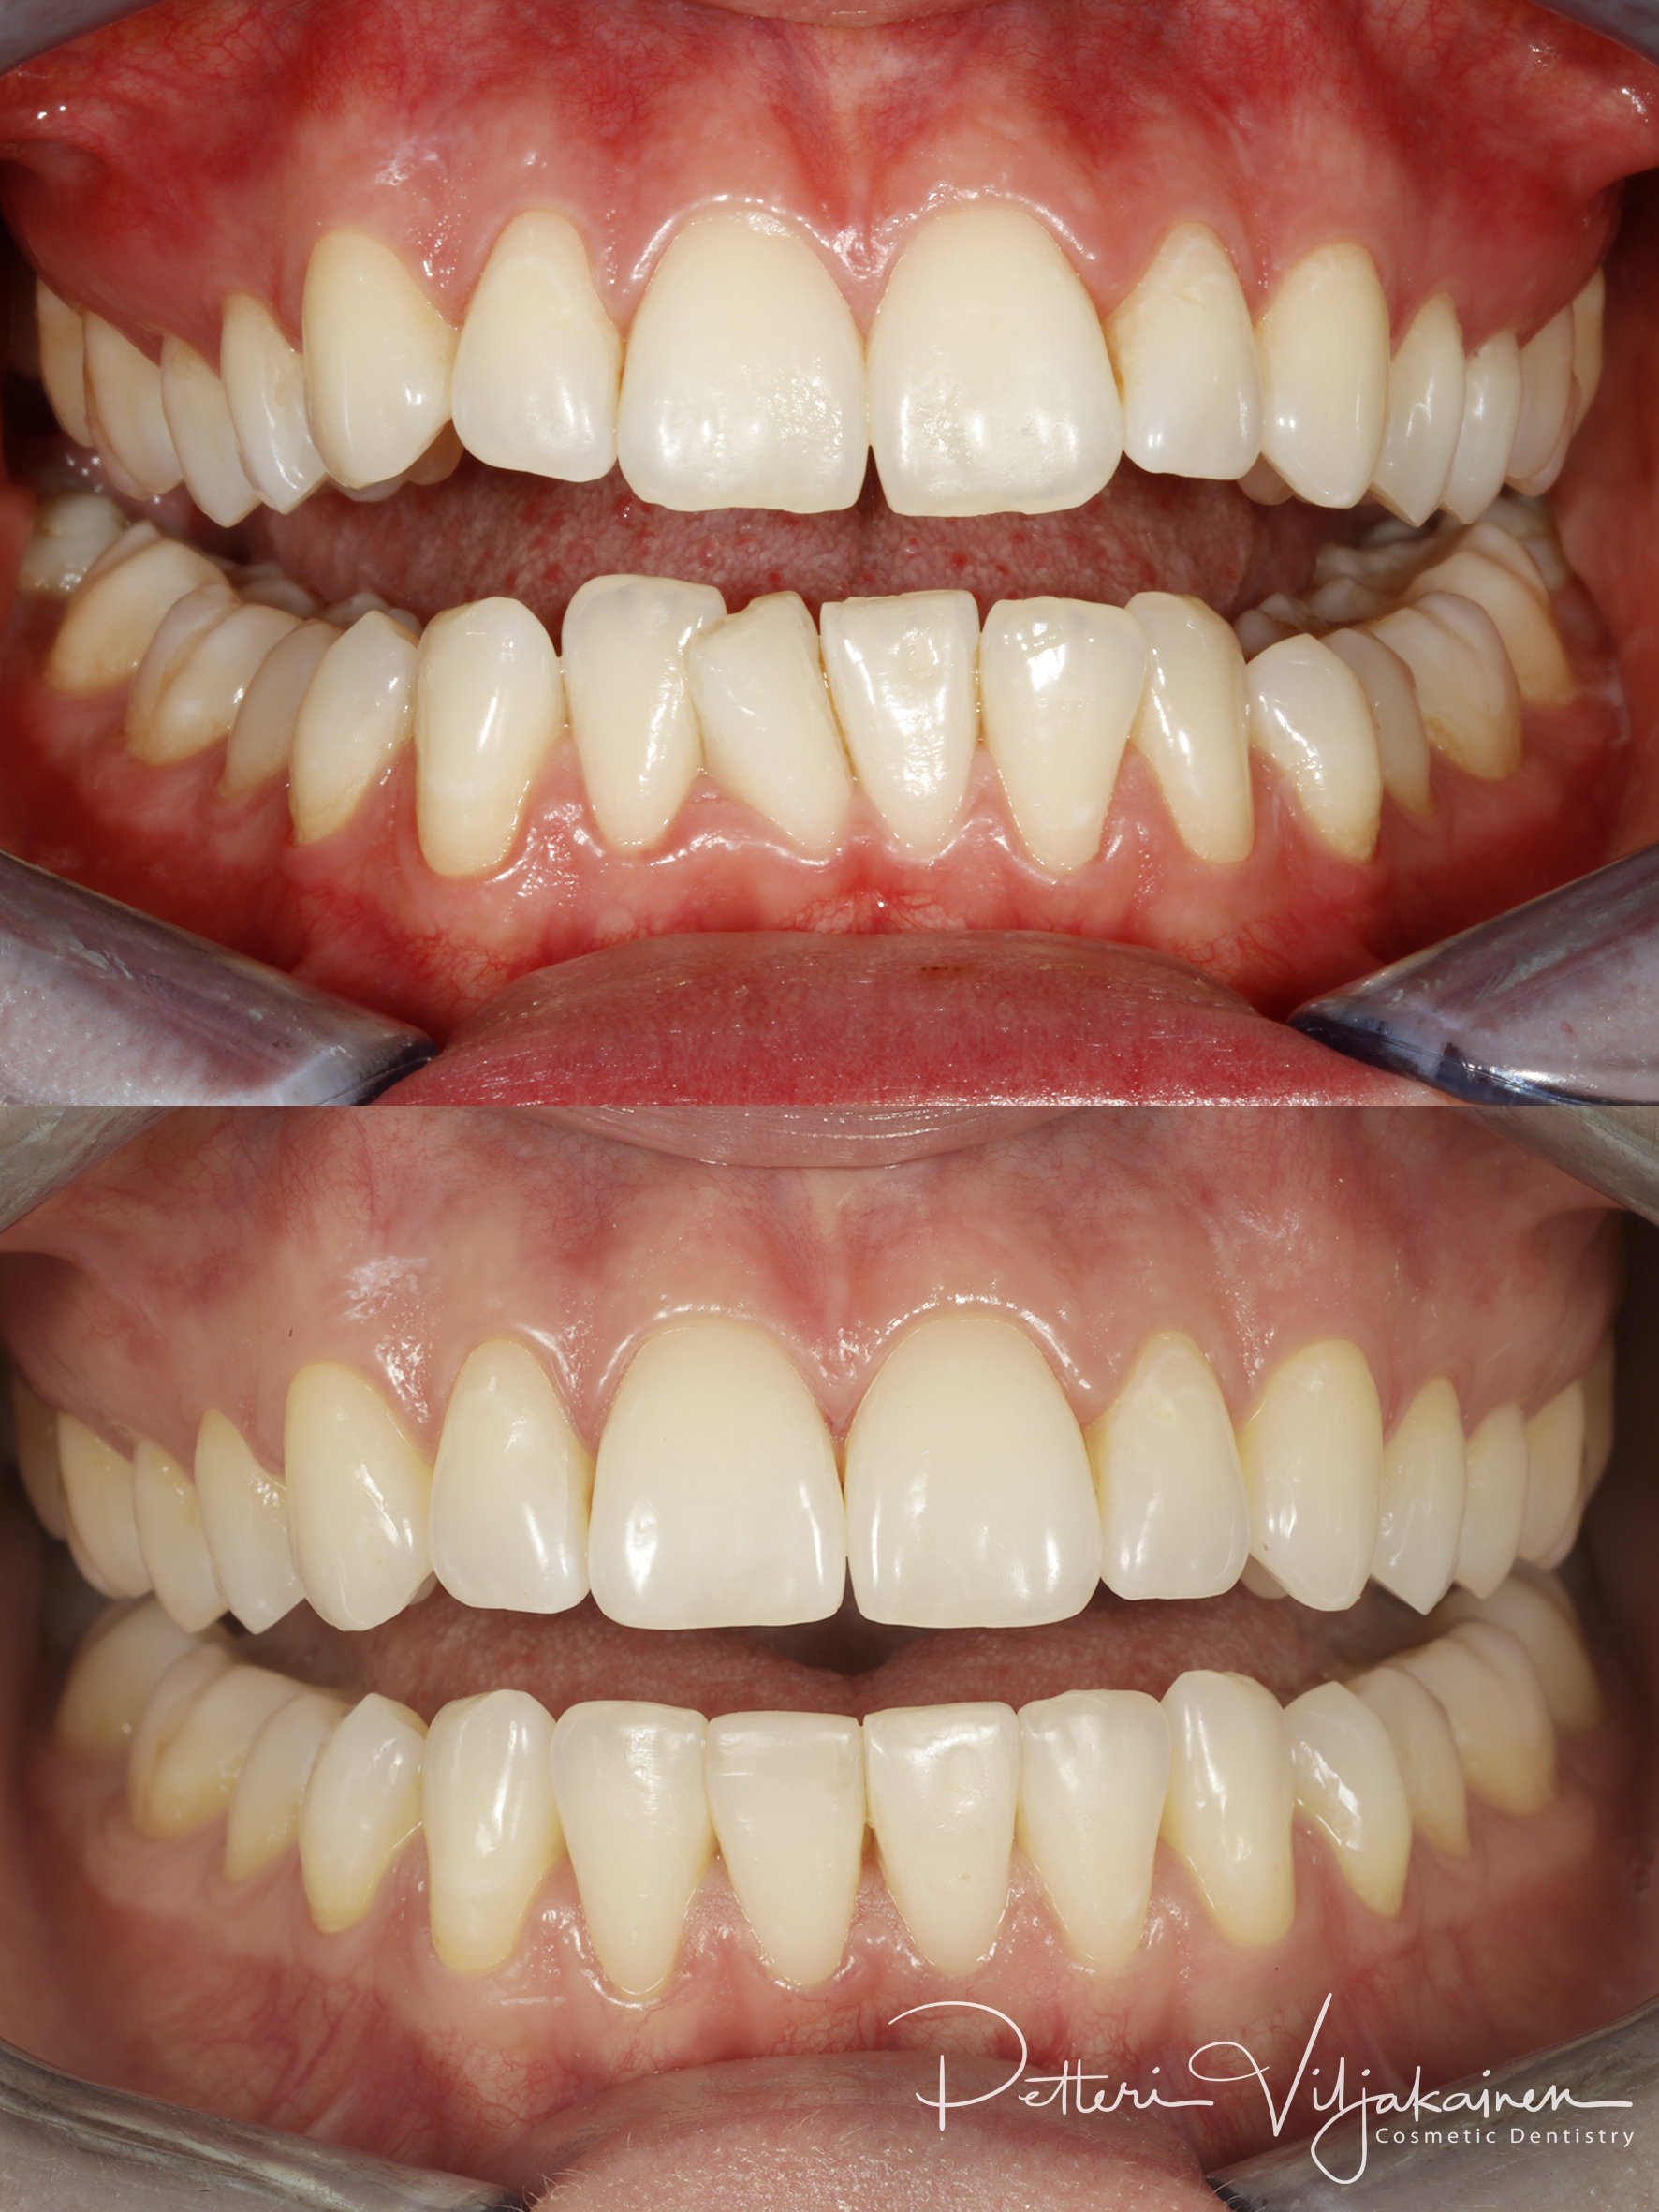

10kk hoito (Comprehensive). Etuhampaiden kärkien viimeistely kerrostusmuoveilla.